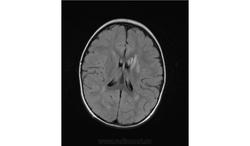

Помогите пожалуйста при постановке диагноза

Ребенок 2 года, заболели в середине декабре, гемипорез, к сожелению не могу ни как с контрасном исследованеим здесь загрузить но накапление контрасного вещества нет, спосибо за помочь!!!!!!!

Предположу гипоксически-ишемические изменения с диапедезным кровоизлиянием. Но они чаще двусторонние.